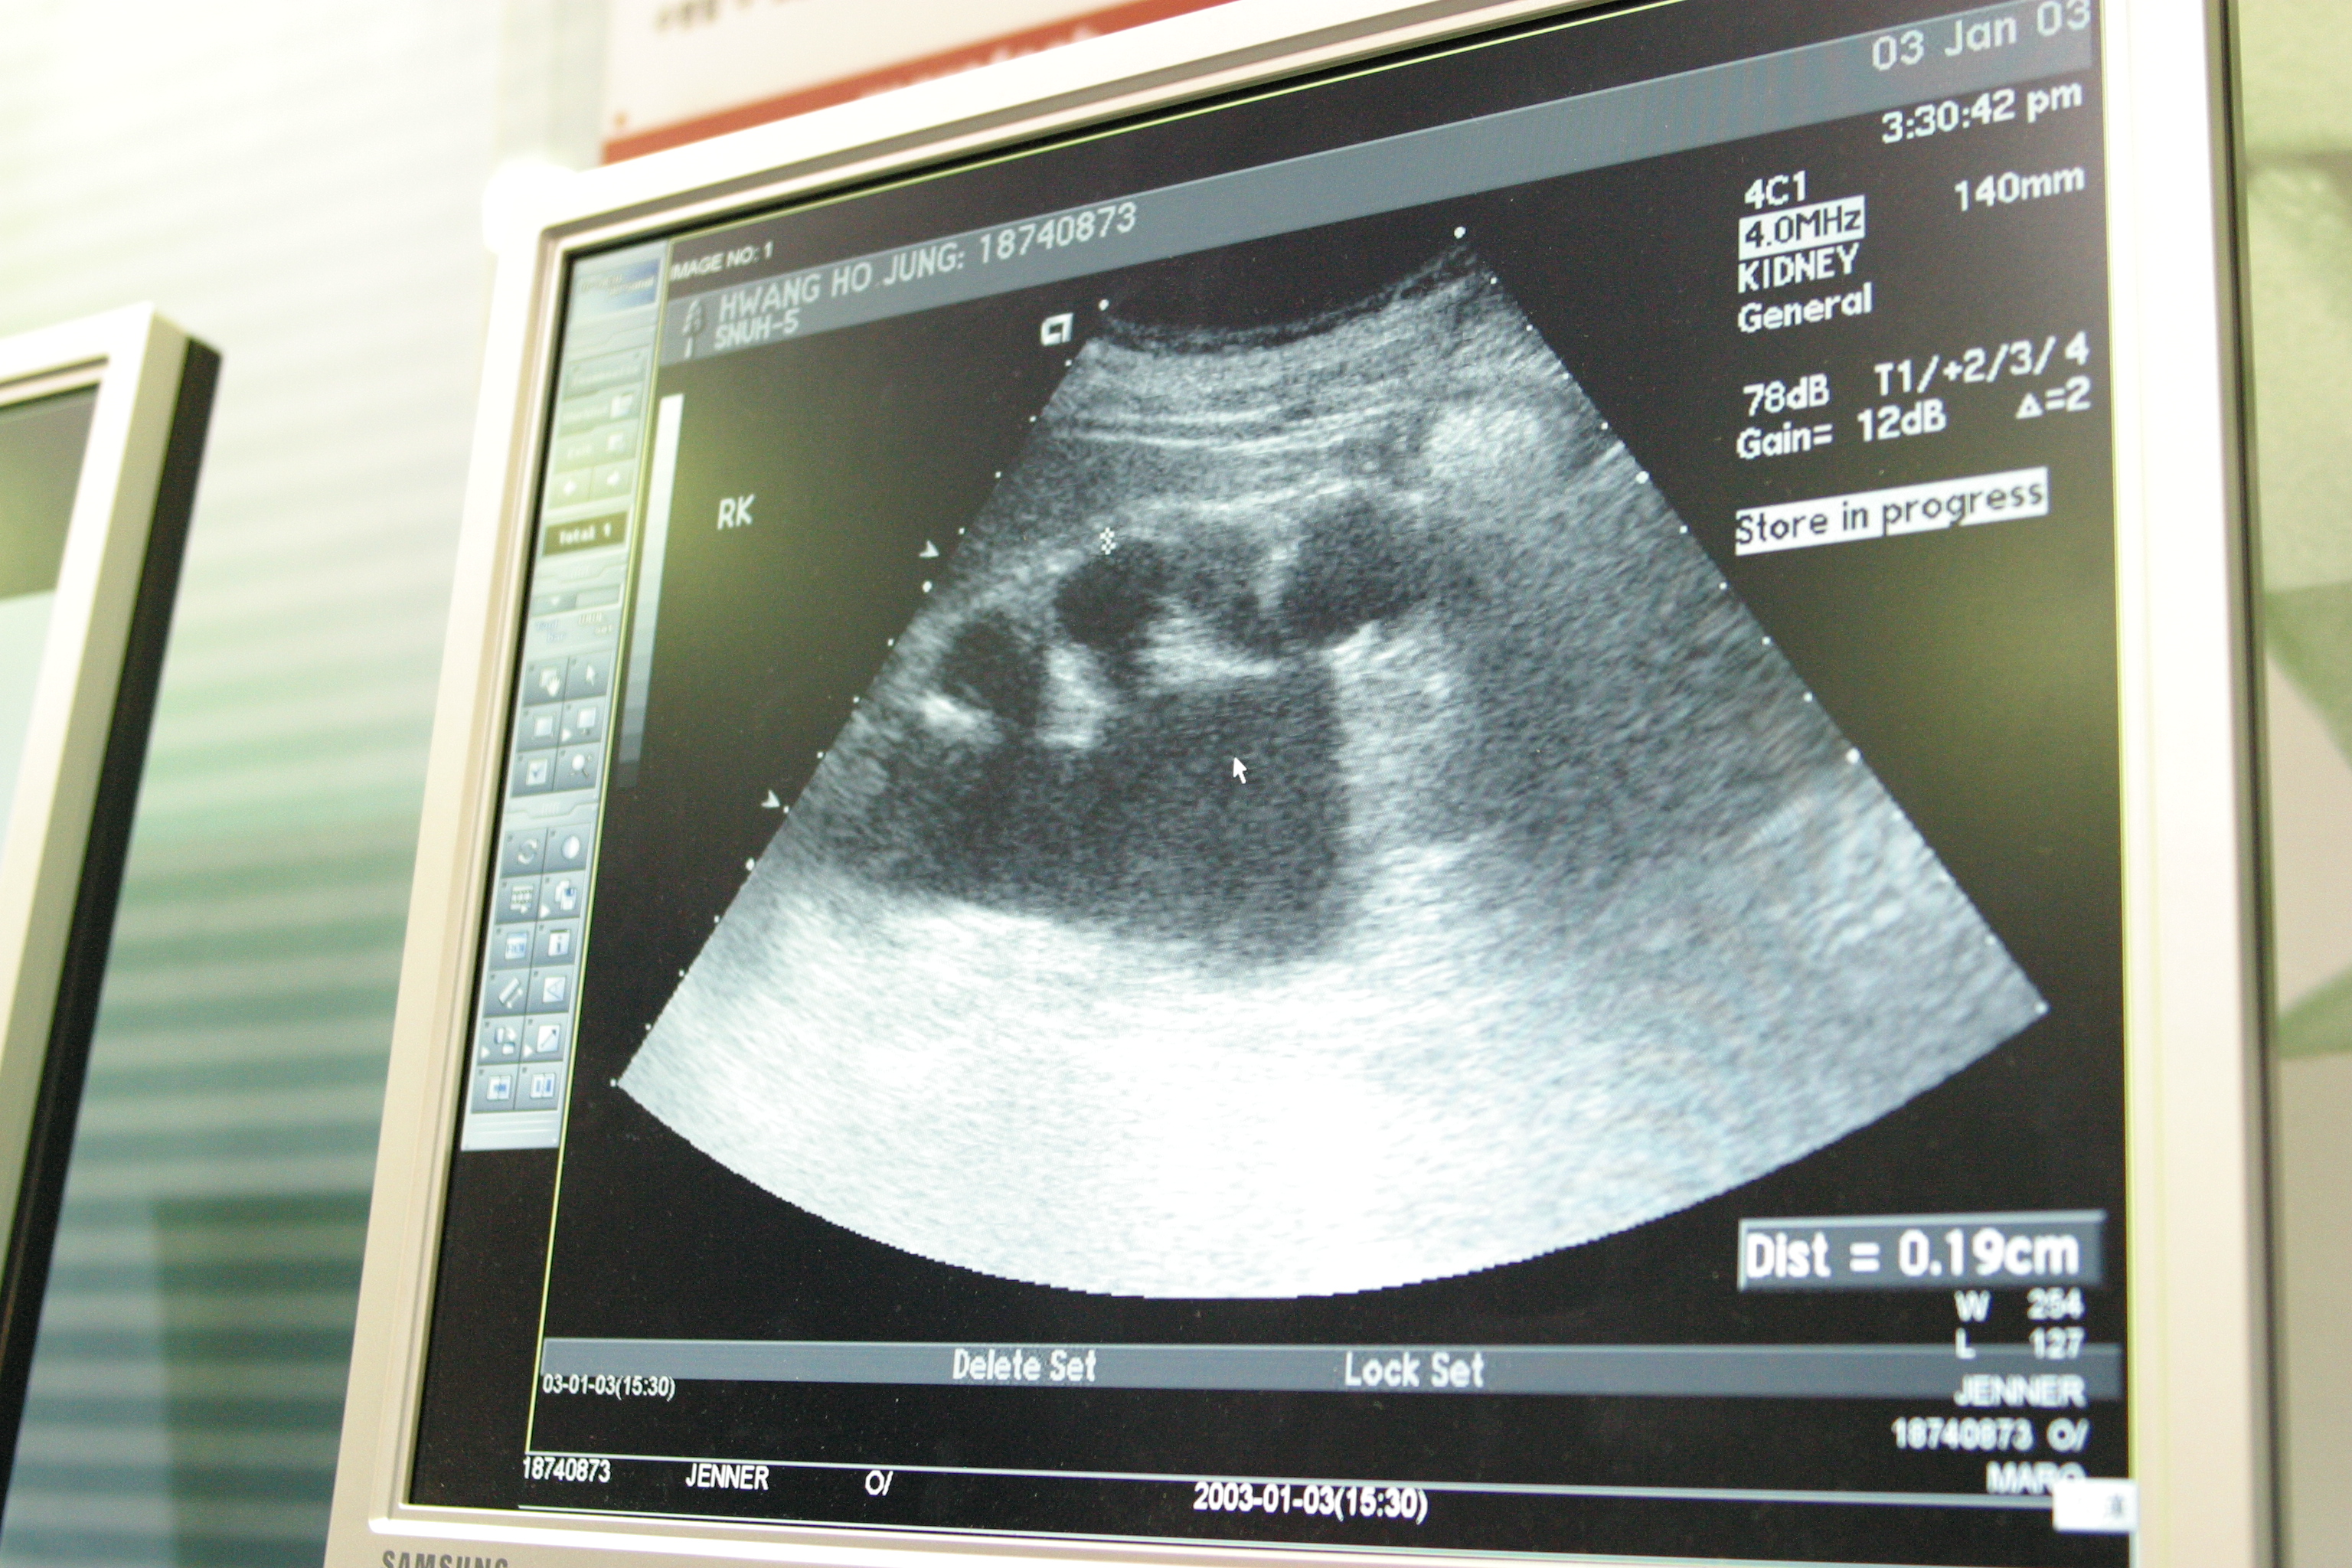

관내 유일한 외래 산부인과의 필수 의료장비인 초음파기와 태아감시장치는 도입된 지 10년이 지나 이미 장비의 수명이 다했습니다.

수명이 다한 낡은 장비는 태아의 미세한 기형이나 이상 징후를 발견하기 어렵습니다.

심지어 센서 감도가 낮아 산모의 맥박과 태아의 심박동조차 제대로 구분하지 못하는 실정입니다.

▲ 건양대학교부여병원의 노후 된 장비 모습들 (좌)초음파기 (우)태아감시장치 ©부여군

⚠️ 초음파기 : 2015년 도입되어 10년 넘게 사용 중입니다.

해상도가 떨어져 미세한 구조적 결함을 식별하기가 어렵고 초기 병변 발견이 힘든 상황입니다.

산전 관리의 핵심은 고성능 초음파를 통해 태아의 기형이나 발달 이상을 조기에 발견하는 것입니다.

낮은 해상도로 인해 태아의 상태를 정확히 판독하기 어렵다 보니, 장비에 대한 불신은 커져만 갑니다.